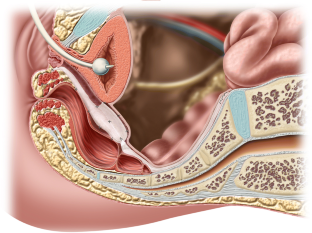

Paramagnetic Fe particles can be added during synthetic mesh production to allow visibility on magnetic resonance imaging. Our aim was to evaluate whether transperineal ultrasound (TPUS) allows visualization, measurement, and characterization of polyvinylidene fluoride (PVDF mesh) containing Fe particles compared with regular polypropylene (PP) meshes used for sacrocolpopexy.

Women up to 1.5 years after laparoscopic sacrocolpopexy who were implanted with a PP or PVDF mesh underwent clinical examination and 2D, 3D, and 4D TPUS. Acquired volumes were analyzed offline for mesh position at rest and maximal Valsalva and for mesh dimensions and characteristics, with the operator blinded to group assignment. The two groups were compared.